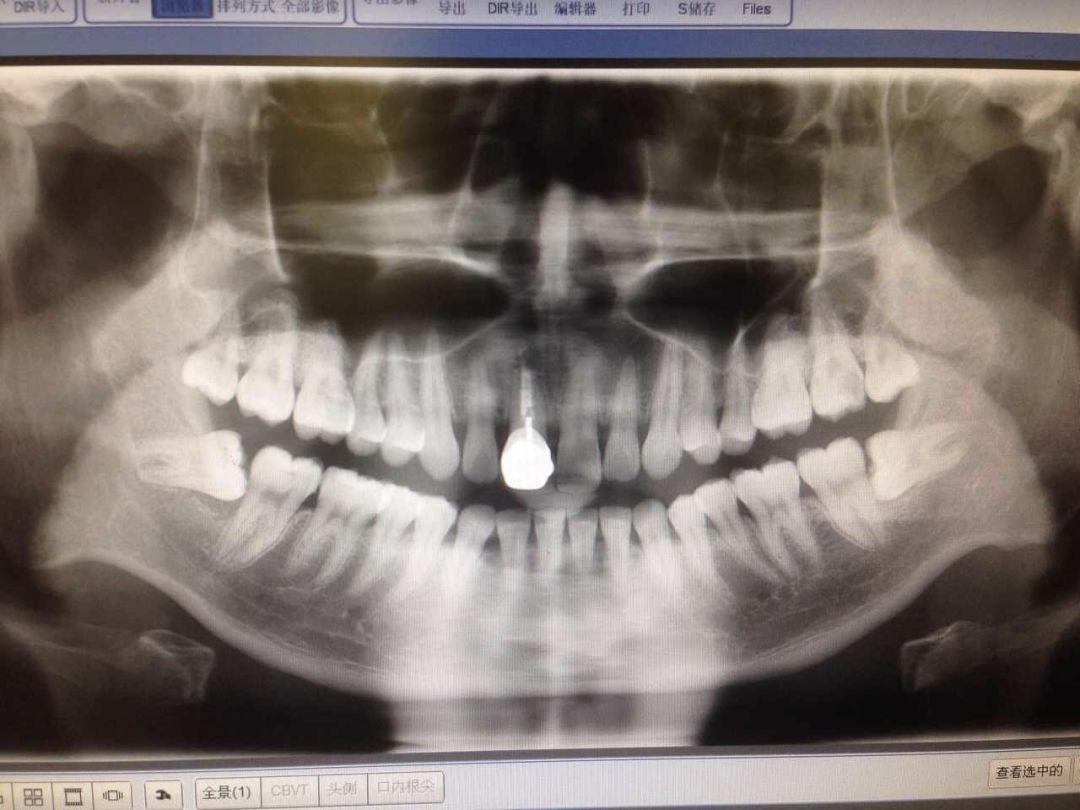

智齒有不同的長(zhǎng)法,我們今天按照 easy - normal - hard - hell 這 4 種難度等級(jí)來(lái)介紹…在拔智齒之前,一般要簽署一個(gè)手術(shù)知情書。拔智齒和普通拔牙不一樣,這都已經(jīng)算是外科手術(shù)對(duì)待了。首先是拍個(gè) 2 維的 X 片或是更精細(xì)的三維的 CT,確定智齒的位置和模樣,牙醫(yī)才能確定拔除方案(和價(jià)格)...

來(lái)帶領(lǐng)大家一起重溫下小編這張牙片,兩顆下智齒都是躺在牙床里的,有一點(diǎn)點(diǎn)頭露出來(lái),和旁邊的牙齒就形成一個(gè)不容易刷到的面。